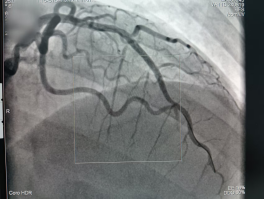

冠脉造影            支架植入术后

14:05,患者直接从急诊科转入导管室;14:10,穿刺成功并置入血管鞘;14:13,冠脉造影显示左冠脉前降支中段急性闭塞;14:20,导丝通过闭塞病变,血管恢复血流,患者胸闷症状显著缓解。后续,医疗团队顺利完成球囊扩张及支架植入,14:40 手术结束,患者安全转入心内科监护病房。从入院到血管开通,全程仅 35 分钟,远低于胸痛中心平均救治时间。